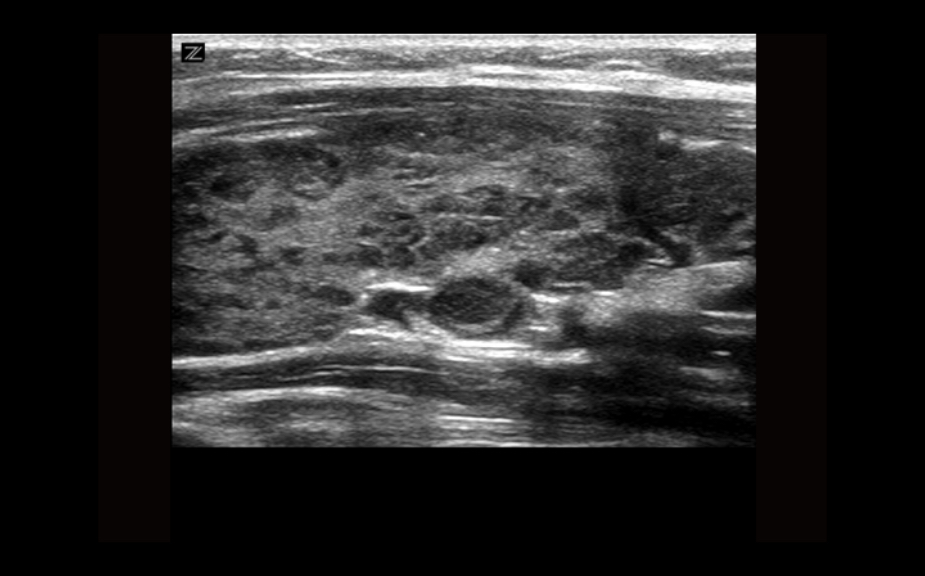

Equipado con software patentado con base en tecnolog├Ła ZONE?Sonography? (ZST),?el Z.One PRO proporciona toma de im├Īgenes Doppler y Modo-B detalladas ├│ptimamente para pacientes, sin importar la complexi├│n del cuerpo, ayudando a asegurar un diagn├│stico confiable.

A trav├®s de una amplia gama de aplicaciones, el Z.One PRO es la soluci├│n de ultrasonido para sus exigentes desaf├Łos cl├Łnicos.

- Insuperable calidad de imagen en todas las aplicaciones

La plataforma de toma de im├Īgenes por ultrasonido Z.One PRO ofrece una familia completa de transductores de peso ligero que incorporan capacidades de banda ancha extendida y flexibilidad multifrecuencia que proporciona una claridad excepcional y una resoluci├│n de detalle mejorada incluso en las mayores profundidades. El transductor C4-1 puede penetrar a trav├®s del campo de visi├│n mientras mantiene una resoluci├│n espacial y de contraste excepcional.